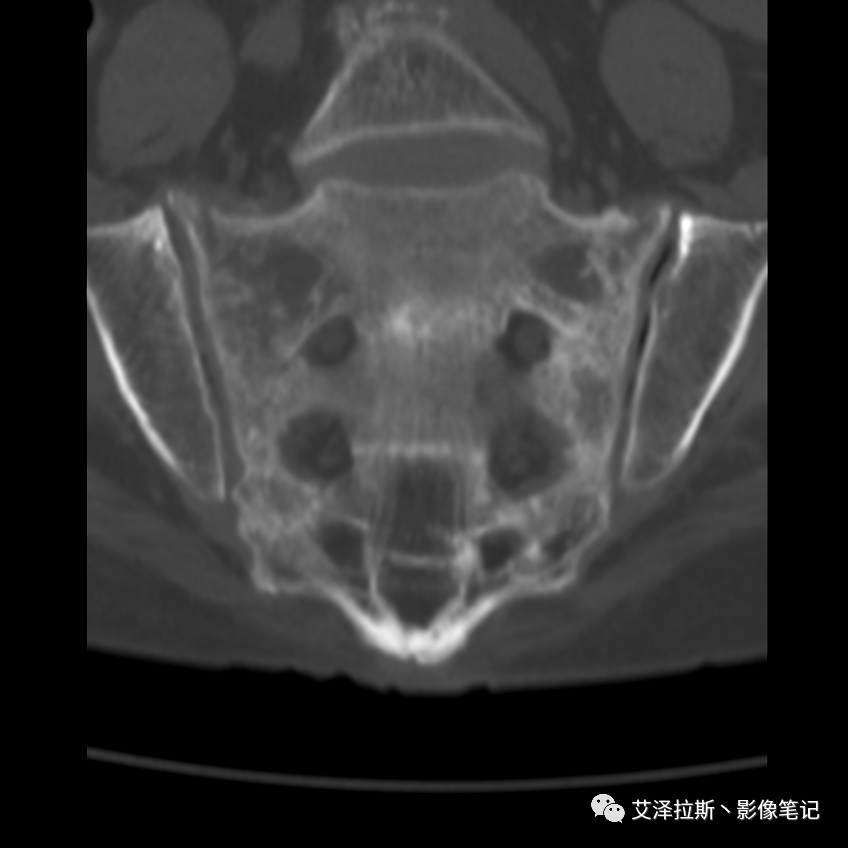

病例2:患者,女性,69岁,老年性骨质疏松症。

病例2

CT平扫:

影像所见

X线、CT:骶骨重度骨质疏松,双侧骶骨翼皮质断裂,分别见迂曲走行的纵行透亮线位于骶孔外侧,大致与骶髂关节间隙平行,骨折端局部可见骨痂、骨质硬化。

诊断意见

骶骨功能不全骨折

①单侧或者双侧骶骨翼骨折,典型者呈“H”形,即“Honda征”;

②骨折线位于骶孔外侧(如下图,主要发生于1区),通常可能会伴随耻骨的功能不全骨折(如:病例2 右侧耻骨上支骨折,L5双侧横突骨折);